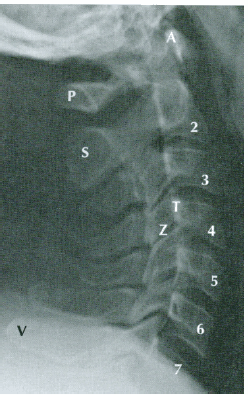

Com base nas informações contidas na figura abaixo, o processo transverso é representado pela letra: